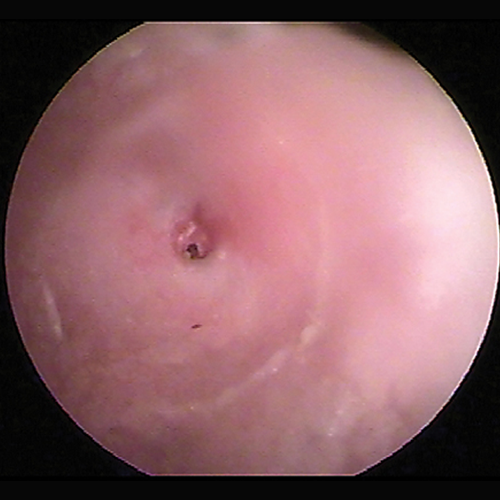

The ear canal is lined by a modified epidermis. The wide vertical ear canal contains hairs surrounded by sebaceous glands, as well as aprocrine glands unassociated with hair follicles. The normal vertical ear canal glistens because of the cerumen coating (Figure 3). On examination of the ear canal with the otoscope, the skin of the vertical and horizontal ear canals should be nonerythematous. The epithelium of the ear canal is smooth. A network of blood vessels in the dermis is present.

Otoscopic image of normal internal ear canal in a dog.

FIGURE 3

Normal canine vertical canal. Blood vessels are visible in the dermis through the thin epithelium. A glistening coating of cerumen is present on the epithelial surface.